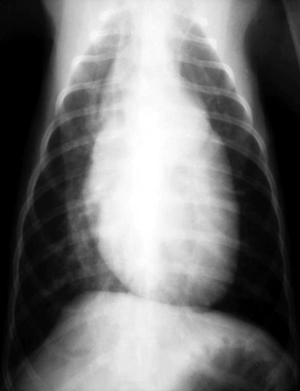

What do chest radiographs show?

Radiographic findings depend on the size of the ductus. Small PDA may cause only mild or no radiographic changes. Larger defects often result in cardiomegaly and signs of increased pulmonary blood flow.

Lateral thoracic radiograph of a dog with PDA DV thoracic radiograph of a dog with PDA